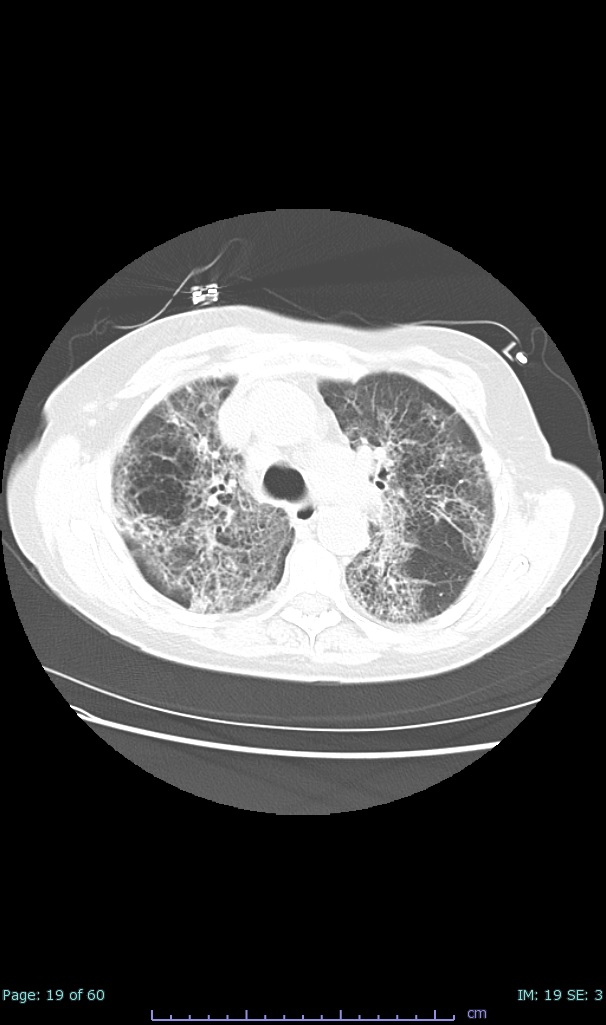

- 100% subpleural involvement, 33% + centrolobular involvement

- 40% even apical/basilar, 27% basilar dom, 5% mid dom. 1/17

- 66% had some + CXR finding I could correlate to a CT finding